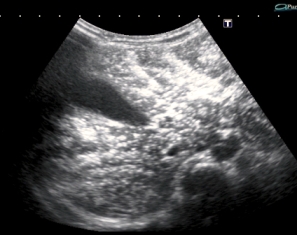

В продолжение темы - сходный случай. Ребёнок 5 мес, поступил с признаками энтеральной недостаточности и вздутым животом.

На рентгенограмме - множественные горизонтальные уровни в просвете кишки, контрастирования газа в проекции печени нет(к слову - иллюстрация того, что горизонтальные уровни в кишечнике не обязательно признак кишечной непроходимости, стул у ребёнка кашицеобразный за последние 12 часов - 4 раза)

На УЗИ - множественные гиперэхогенные включения в печени. Через 2 дня живот опал, на УЗИ - нормальная печень. Признаков некроза кишечника не было.

Рискну высказать предположение о возможности проникновения газа в портальную систему через неповреждённую, но восппалённую стенку кишки на фоне избыточного давления в её просвете .